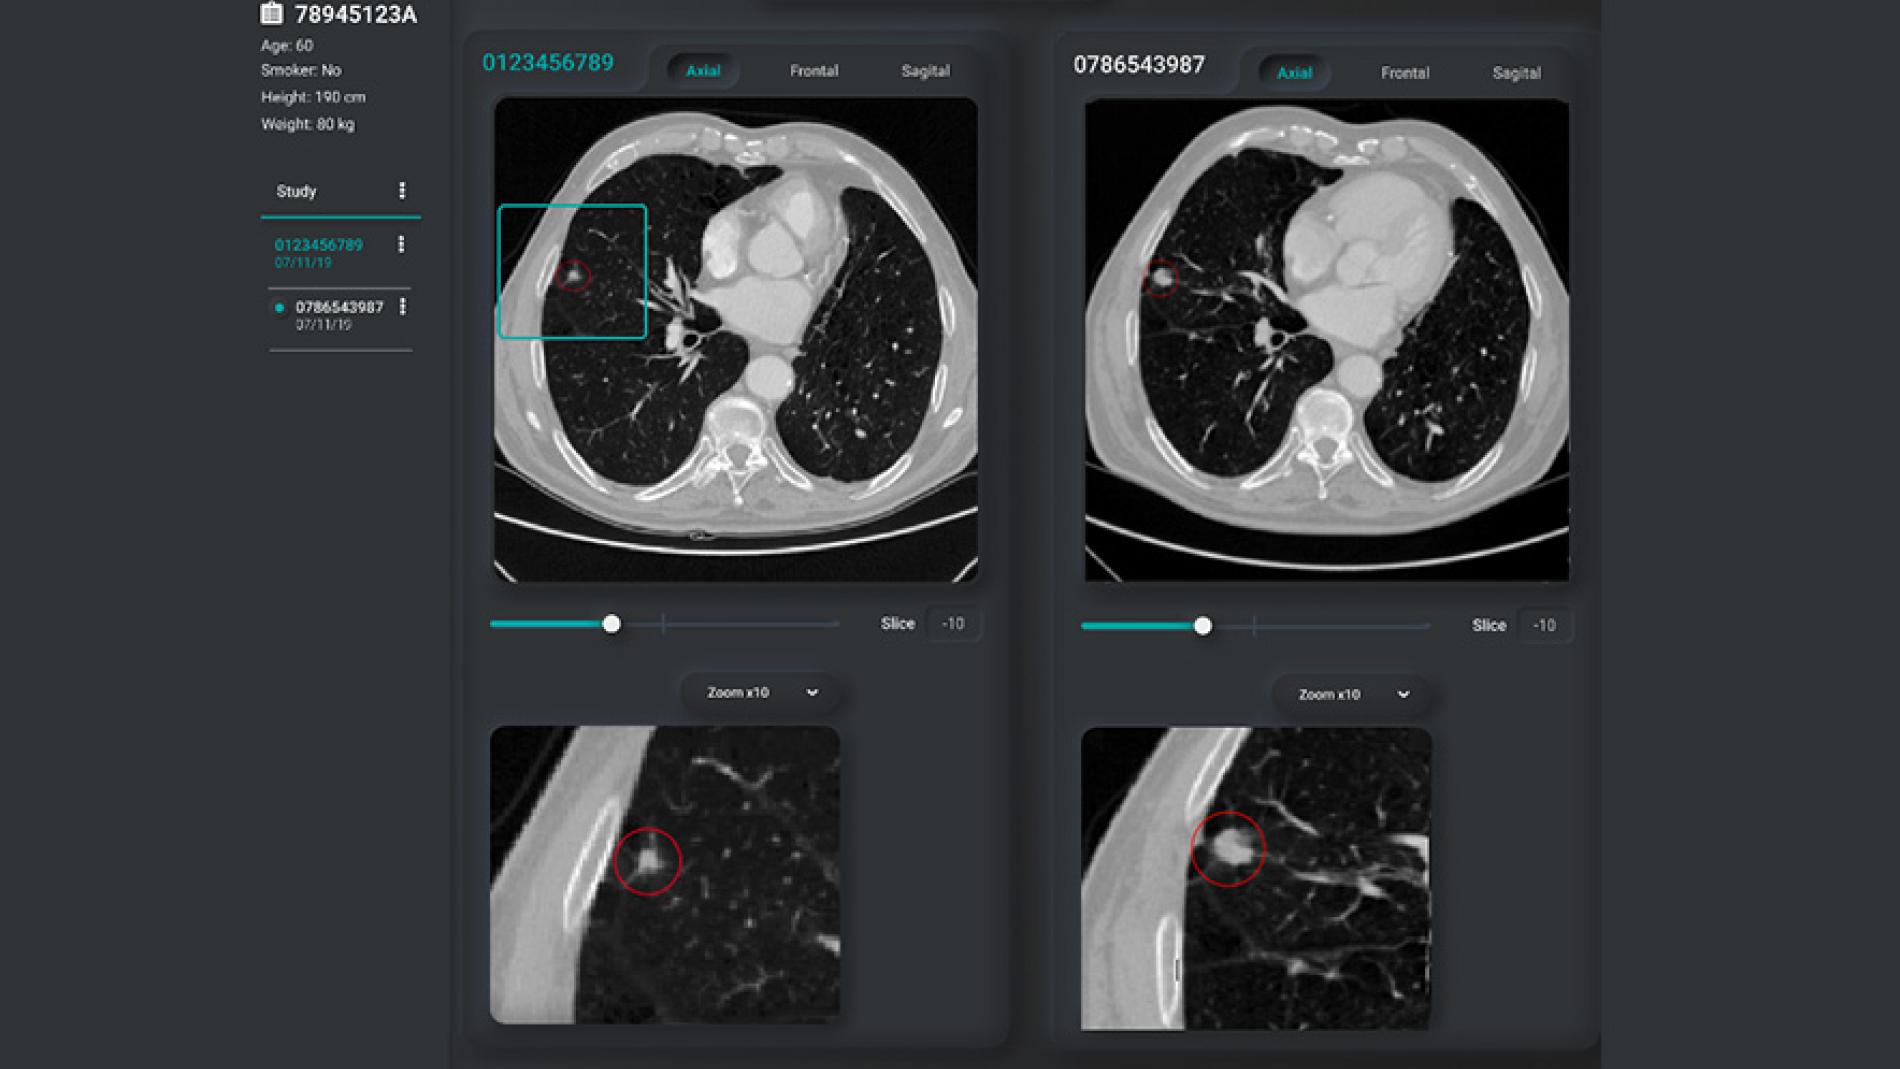

El Campus Vall d'Hebron, juntament amb el centre tecnològic Eurecat, ha creat un nou sistema per a la identificació de nòduls indicadors de possibles càncers pulmonars mitjançant una eina basada en tècniques d'Intel.ligència Artificial, en concret, de Deep Learning o aprenentatge profund. El projecte ha comptat amb el suport del CIDAI (Centre d'Innovació en Tecnologies de Dades i Intel.ligència Artificial). Eurecat ha mostrat la tecnologia en la vigent edició del Mobile World Congress.La tecnologia permet l'entrenament de models predictius a partir d'imatge mèdica 3D, integrada amb el flux de treball de radiologia, amb la finalitat de "fer possible la detecció precoç de la malaltia i proporcionar una eina de suport al pronòstic i al seguiment per part dels professionals mèdics experts, un avenç en medicina de precisió que està transformant la pràctica clínica i el sector de la salut", explica el director de la Unitat de Digital Health d'Eurecat, Felip Miralles.La innovació està orientada a donar suport als radiòlegs en el seguiment dels nòduls pulmonars, mitjançant un sistema capaç d'executar anàlisis a través d'aprenentatge profund, capaç de detectar nòduls i reidentificar-los, proporcionant una projecció de creixement i la probabilitat de ser cancerígens.Un element important d'aquesta innovació ha estat la creació d'una interfície per executar l'anàlisi temporal dels nòduls pulmonars i examinar visualment els resultats, d'una manera intuïtiva i informativa, per ajudar els metges a proporcionar diagnòstics més precisos.Aquesta eina ha estat desenvolupada per Eurecat amb la col.laboració del Campus Vall d'Hebron coordinada per la Direcció Clínica de Diagnòstic per la Imatge i Medicina Nuclear de l'Hospital,, en el marc del projecte Deep Lung. "L'objectiu és desenvolupar una eina d'intel.ligència artificial (IA) aplicada a les imatges de Tomografia Computeritzada per detectar precoçment el càncer de pulmó. Aquesta eina està basada en el seguiment de lesions sospitoses, avaluades pels metges especialistes en Radiologia de Vall d'Hebron. L'aplicació de la IA en aquests casos permetrà millorar la capacitat diagnòstica i predictiva en pacients afectats per la malaltia i en futurs programes de cribratge poblacional de càncer de pulmó", conclou el Dr. Manel Escobar, Director Clínic del Servei de Diagnòstic per la Imatge de l'Hospital Universitari Vall d'Hebron i investigador del grup d'Imatge Mèdica Molecular del Vall d'Hebron Institut de Recerca (VHIR).